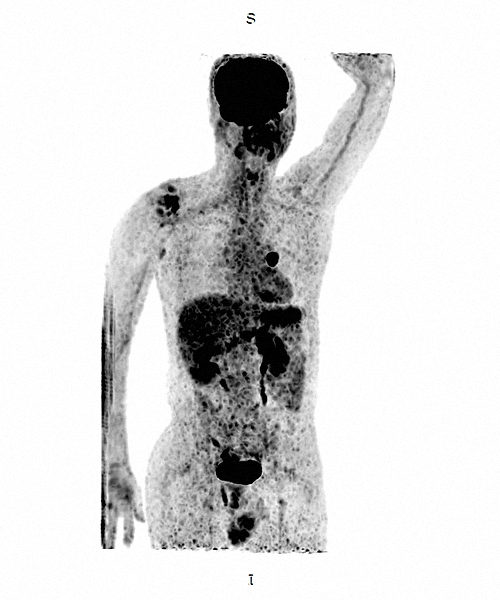

Cintilografia

Presente na medicina nuclear, esse exame utiliza pequenas quantidades de materiais emissores de radiação, eles formarão imagens diagnósticas.

A medicina nuclear é capaz de detectar anormalidades que nenhum outro método consegue, por isso realize seus exames no Ultra-X. Conheça nossos serviços: Miocárdio, Tireoide, Metástase, Renal, Cerebral, Fígado e baço, Glândulas salivares, Vias biliares, Testicular, Óssea, Mama, Pulmonar.